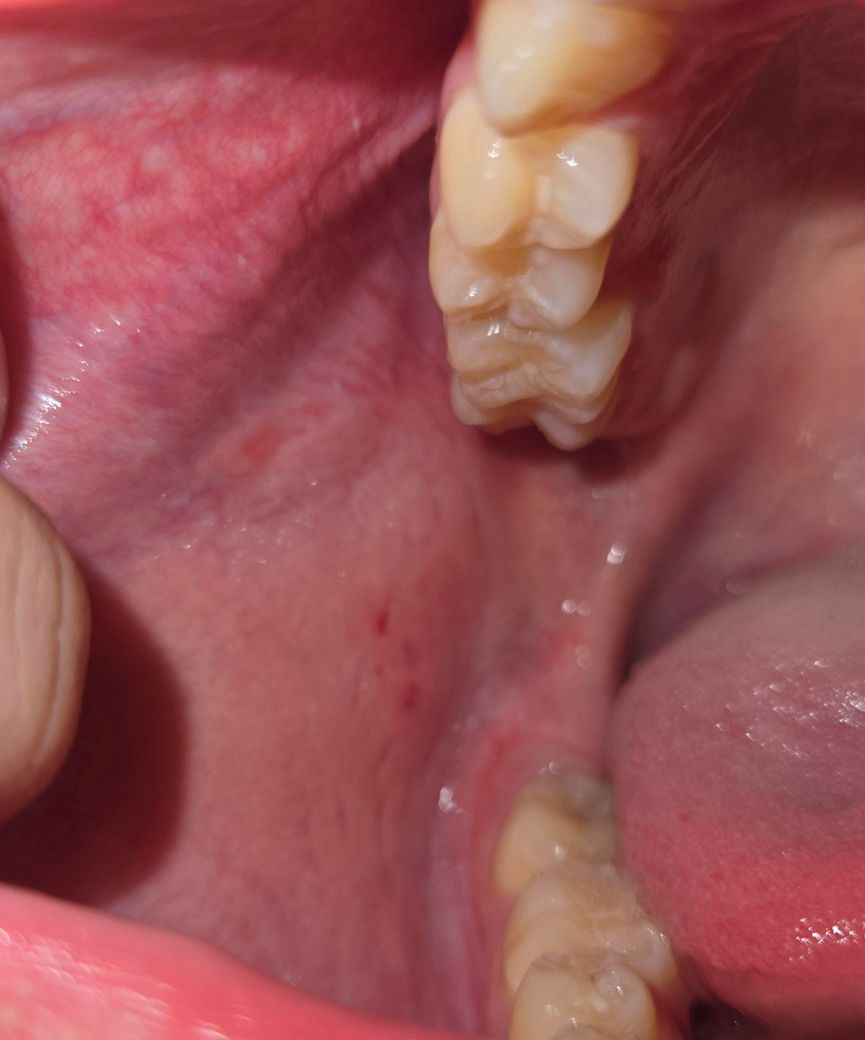

입 안쪽에서 허물 같은 것이 나옵니다.

최근에 입안에서 하얀 허물이 벗겨져서 나오고 입안을 부풀었다가 입안에 있는 공기를 내불면 하얀 가루 같은 것들이 나옵니다. 그리고 입안 볼 쪽에 하얀 허물 덩어리들도 붙어있을 때도 있습니다. 입안도 헌 것 같은데 어떻게 대처해야 하나요? 그리고 왜 하얀 허물 같은 게 왜 생기는 거죠?

• 1번 째 사진

해당 부분이 구내염 등의 구강 내 연조직 질환인지, 입안이 건조해서 나타나는 증상인지 혹은 치아 등에 의해서 볼쪽 점막이 손상되었는지 등에 대한 정확한 감별이 필요합니다. 지금으로서는 해당 부분에 대한 정확한 진단이 선행되어야 합니다. 단순 구내염이나 일시적으로 치아로 인한 손상이라면 수일이나 수주 이내에 회복됩니다.

볼살이 치아에 씹히면서 볼살 표피가 벗겨지는거 같습니다. 볼살이 치아에 씹히지 않도록 조심하시면될것같습니다.

사진상으론 명확히 알기 어려우나 증상을 보면 곰팡이, 세균 감염이 의심됩니다 치과가서 항생제 처방이 필요할지 상담받아보시기 바랍니다